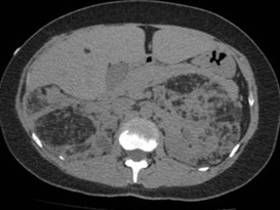

Angiomiolipoma renal à direita

Angiomiolipoma renal bilateral

Angiomiolipomas renais